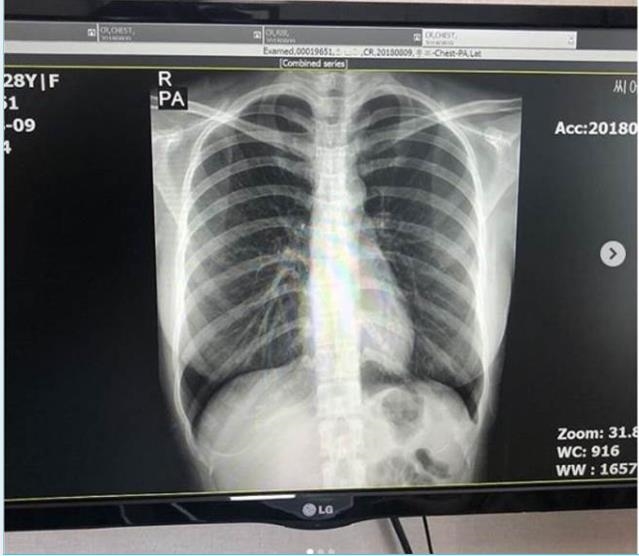

身高170公分、體重54公斤的崔素美,擁有令人稱羨的完美比例。傲人的曲線、纖細的腰肢與修長的美腿相得益彰,形成極具吸引力的S形身段,每一次在鏡頭前擺姿,都彷彿是精雕細琢的藝術品,輕微的肢體動作便能讓粉絲為之心動。不過過去曾有酸民質疑她的胸部是「人工製成」,對此她霸氣曬出X光片力證真身,強調全是天然、毫無填充物。